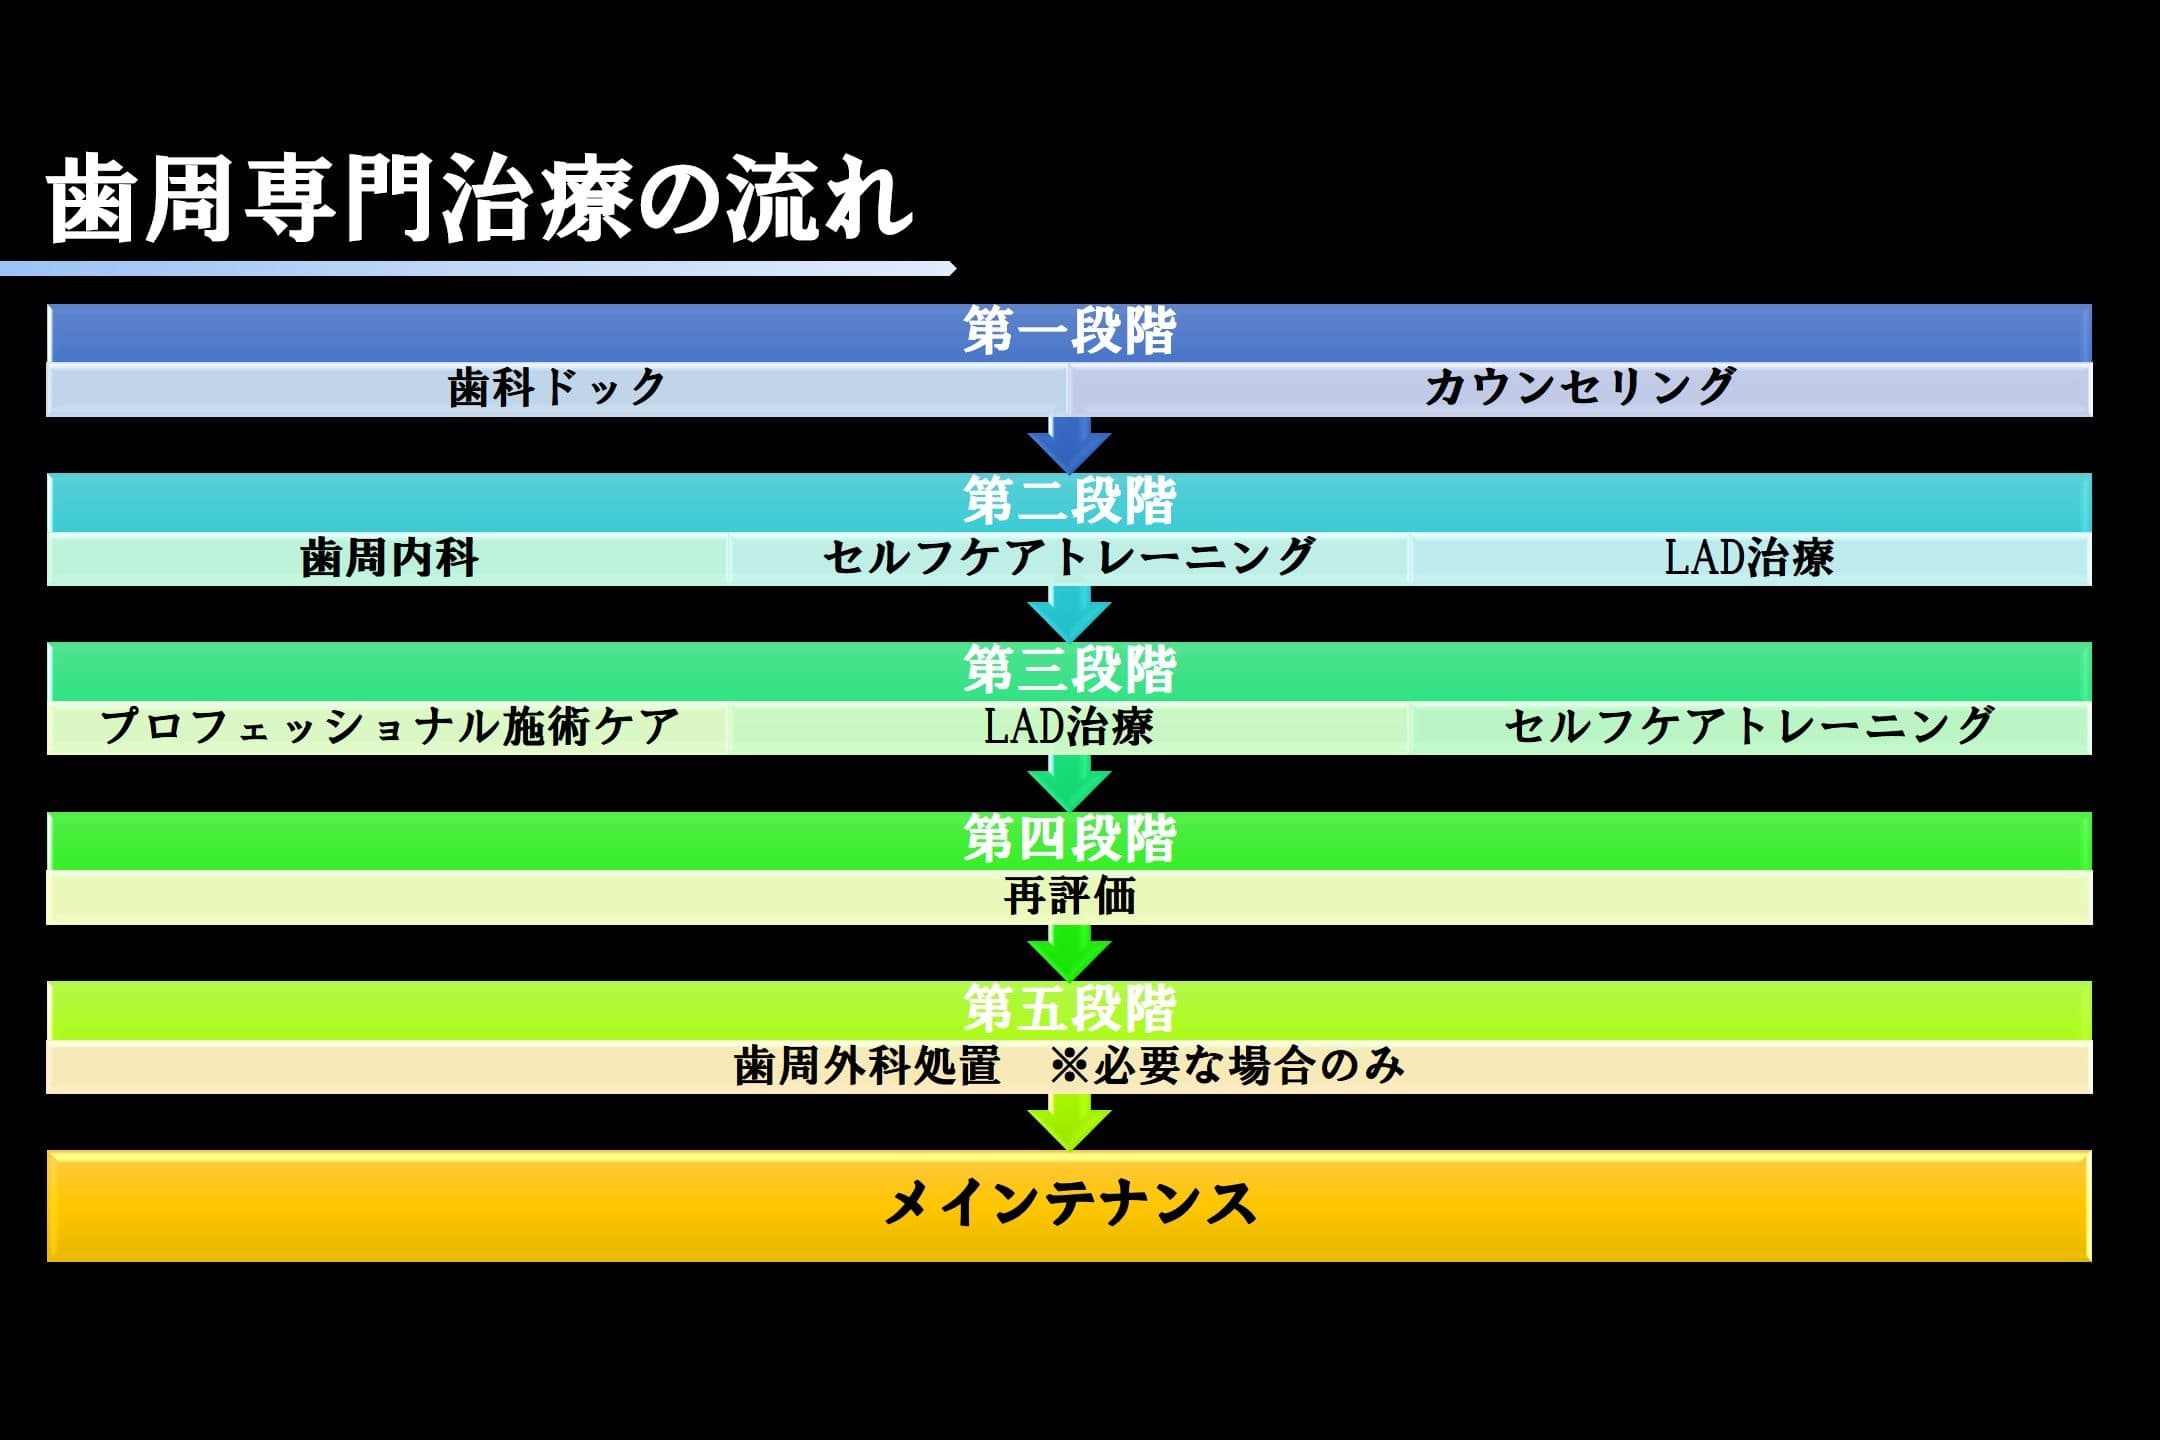

歯周専門治療(セルフケアトレーニング)

こんにちは。 南館歯科クリニックの歯科衛生士の山崎です。 今回ご紹介する歯周専門治療のケースは、治療初期に行われる、ご自宅でのケア(セルフケアトレーニング)についてお伝えします。 (下図は、全体の流れ…